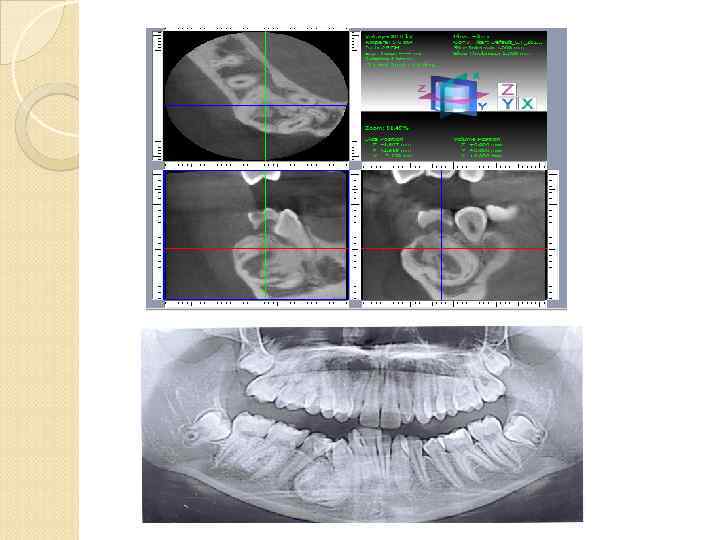

Однако для визуализации всех необходимых анатомических структур, выявления анатомо-топографических особенностей и патологических процессов челюстей вышеперечисленных методов рентгенографии бывает недостаточно рентгенограмма является двухмерным суммационным изображением и не позволяют исследовать объекты в

Однако для визуализации всех необходимых анатомических структур, выявления анатомо-топографических особенностей и патологических процессов челюстей вышеперечисленных методов рентгенографии бывает недостаточно рентгенограмма является двухмерным суммационным изображением и не позволяют исследовать объекты в

вследствие обязательных проекционных искажений, обусловленных технологией получения рентгенограмм, сложно произвести точные измерения.

вследствие обязательных проекционных искажений, обусловленных технологией получения рентгенограмм, сложно произвести точные измерения.

У пациентов с дефектами зубных рядов при подготовке к имплантации ортопантомограммы не всегда позволяют точно оценить степень атрофии альвеолярных отростков в различных плоскостях, четко рассчитать расстояние от альвеолярного гребня до важных анатомических образований

У пациентов с дефектами зубных рядов при подготовке к имплантации ортопантомограммы не всегда позволяют точно оценить степень атрофии альвеолярных отростков в различных плоскостях, четко рассчитать расстояние от альвеолярного гребня до важных анатомических образований

Спиральная компьютерная томография СКТ дает больше диагностической информации по сравнению с обычной КТ. Возможна реконструкция изображения в любой заданной плоскости Спиральные компьютерные томографы оснащены специальной программой «Dentascan» в различных вариантах. По данным аксиального изображения каждой из челюстей строится кривая, проходящая через центр альвеолярного отростка

Спиральная компьютерная томография СКТ дает больше диагностической информации по сравнению с обычной КТ. Возможна реконструкция изображения в любой заданной плоскости Спиральные компьютерные томографы оснащены специальной программой «Dentascan» в различных вариантах. По данным аксиального изображения каждой из челюстей строится кривая, проходящая через центр альвеолярного отростка

Все типы стандартных программ сложны в применении, без специальной подготовки оператора. Лучевая нагрузка 400 мк. Зв Затруднительно построение кривой через середину альвеолярного гребня с учетом различной степени деформации и толщины кортикальной

Все типы стандартных программ сложны в применении, без специальной подготовки оператора. Лучевая нагрузка 400 мк. Зв Затруднительно построение кривой через середину альвеолярного гребня с учетом различной степени деформации и толщины кортикальной